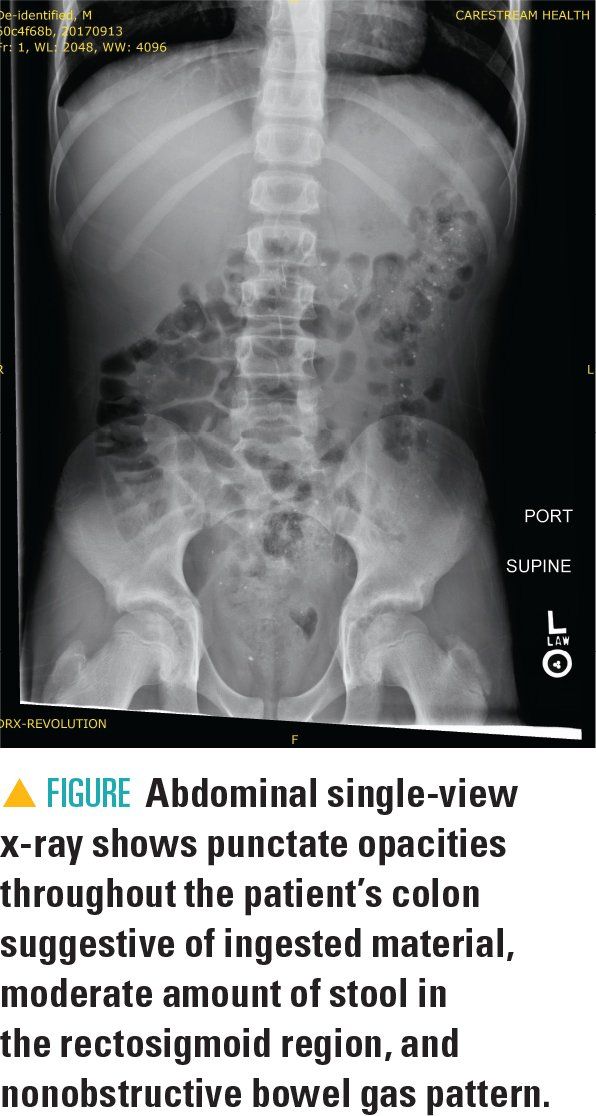

The patient was admitted for observation because of concern for early/possible retrocecal appendicitis. The following day, abdominal single-view x-ray was performed to evaluate constipation (Figure) and revealed punctate opacities equally distributed throughout the colon suggestive of ingested material, a moderate amount of stool in the rectosigmoid colon, and a nonobstructive bowel gas pattern.

The abdominal radiograph observed in this patient was novel to the Radiology Department and concerning for possible ingestion of lead, antacids, bismuth medication, or heavy metal. Differential diagnosis ranged from ingestion of a radiopaque substance to chronic inflammation (Table).